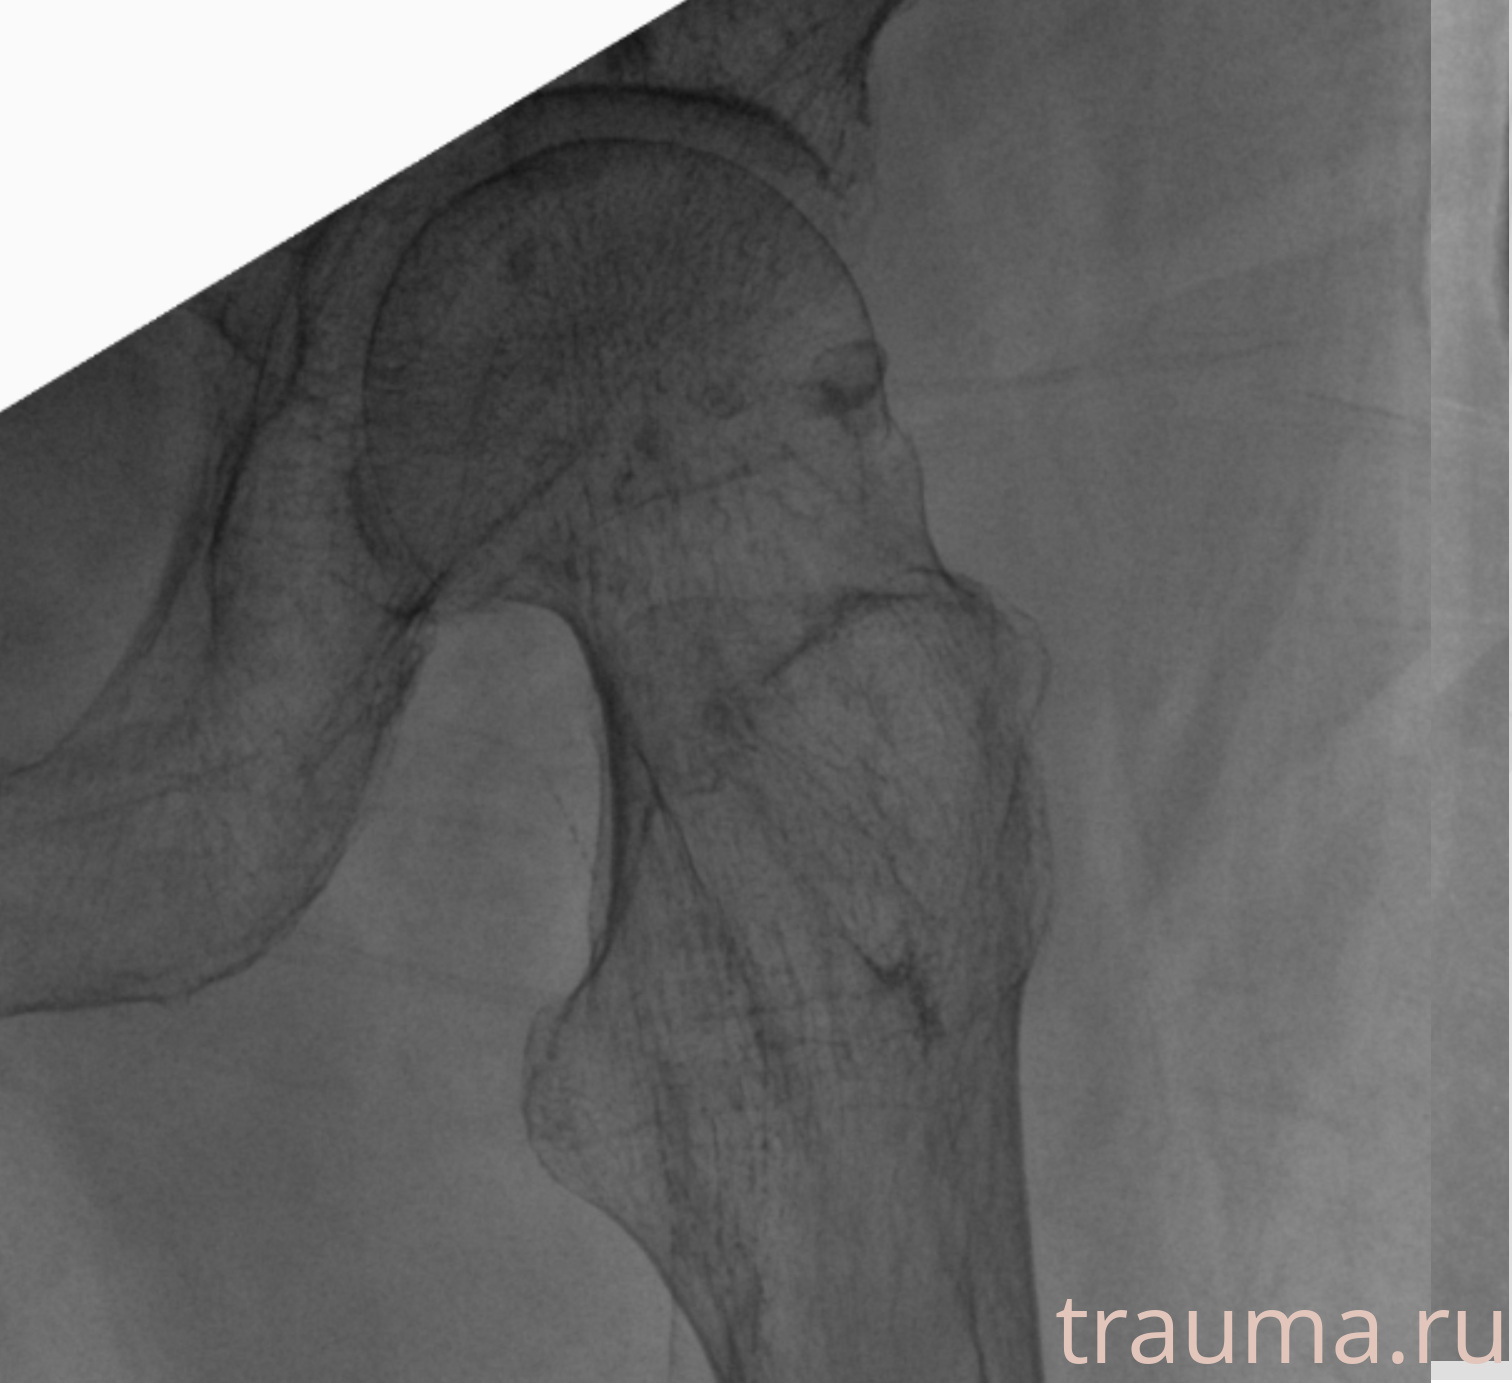

Рентгенограммы

Рентген на дому: по вашему адресу приезжает врач-рентгенолог, травматолог-ортопед с мобильным рентгеновским аппаратом, проводит диагностику травмы или заболевания, делает необходимые рентгенограммы, дает рекомендации по дальнейшему лечению. Получить качественные снимки в домашних условиях возможно благодаря уникальной методике, разработанной МосРентген Центром для института  Склифосовского